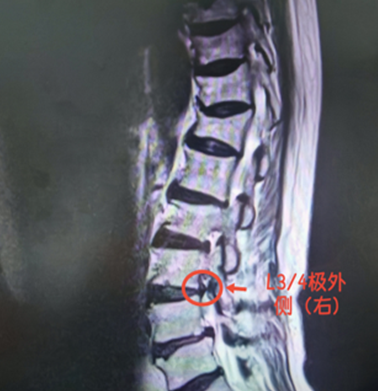

为何它能躲过一次次检查?王医生解释,普通腰椎间盘突出多 “向后外、向后” 压迫神经,而极外侧突出则 “向侧面” 钻进神经根出发的狭窄通道(椎间孔及椎间孔外侧),这就导致三大问题: 症状 “打游击”:患者疼痛多累及同节段神经根,而非普通类型的下位神经根,常表现为剧烈下肢放射痛,腰痛却较轻微,极易被误判为髋关节或下肢疾病; 检查易 “漏网”:常规 CT 平扫横断面上,椎管内无明显异常,需通过薄层 CT 精确扫描椎间孔内及外侧区,才能发现低密度软组织团块;MRI (核磁共振)上则可见椎间孔内神经根显影不清、受压迫。“临床医师阅片时习惯关注椎管内情况,易忽略椎间孔区及外侧区,导致漏诊误诊,有研究显示约 30% 的病例首次就诊时被误诊。” 王医生补充道;治疗常“扑空”:椎间孔内空间狭窄,若髓核脱出并上移贴近上位椎弓根下缘,神经根会受压严重,患者会出现持续剧烈根性疼痛,甚至被迫保持特定体位,保守治疗效果往往不佳。 微创手术巧拆 “弹”:7 毫米切口破局 面对这个嵌在骨缝里的“钉子”,我院脊柱外科团队决定采用“椎间孔镜微创手术”——如同通过钥匙孔取出门缝里的沙粒。手术当天,王医生在陈大爷腰部开了一个仅7毫米的小口,在内窥镜引导下精准定位突出物。屏幕上清晰显示:一颗黄豆大小的髓核紧紧卡在L4神经根上,周围已出现水肿粘连。“小心分离,保护神经!”王医生用细钳稳稳夹住突出物并完整取出,被压迫的神经瞬间松弛。术后“奇迹”发生:陈大爷麻醉苏醒后第一时间惊呼:“腿不疼了!太谢谢你们了,不然我不知道还要痛多久!”术后第二天,他便已能独立下床活动。 专家提醒:腰椎间盘突出症多见于20~50岁人群,男性明显多于女性,常表现为反复腰痛,腰骶部至下肢的放射性疼痛发生率极高。预防建议:避免斜坐沙发、突然扭腰搬重物;多做“小燕飞”“平板支撑”,增强腰背肌保护力。极外侧型腰椎间盘突出虽少见,但因易漏诊误诊,常让患者走弯路。陈大爷的经历提醒我们:腿痛不一定是腿部本身的问题,找准病根才能精准施治!如今微创技术的进步,让此类疾病可通过精准手术实现快速康复。